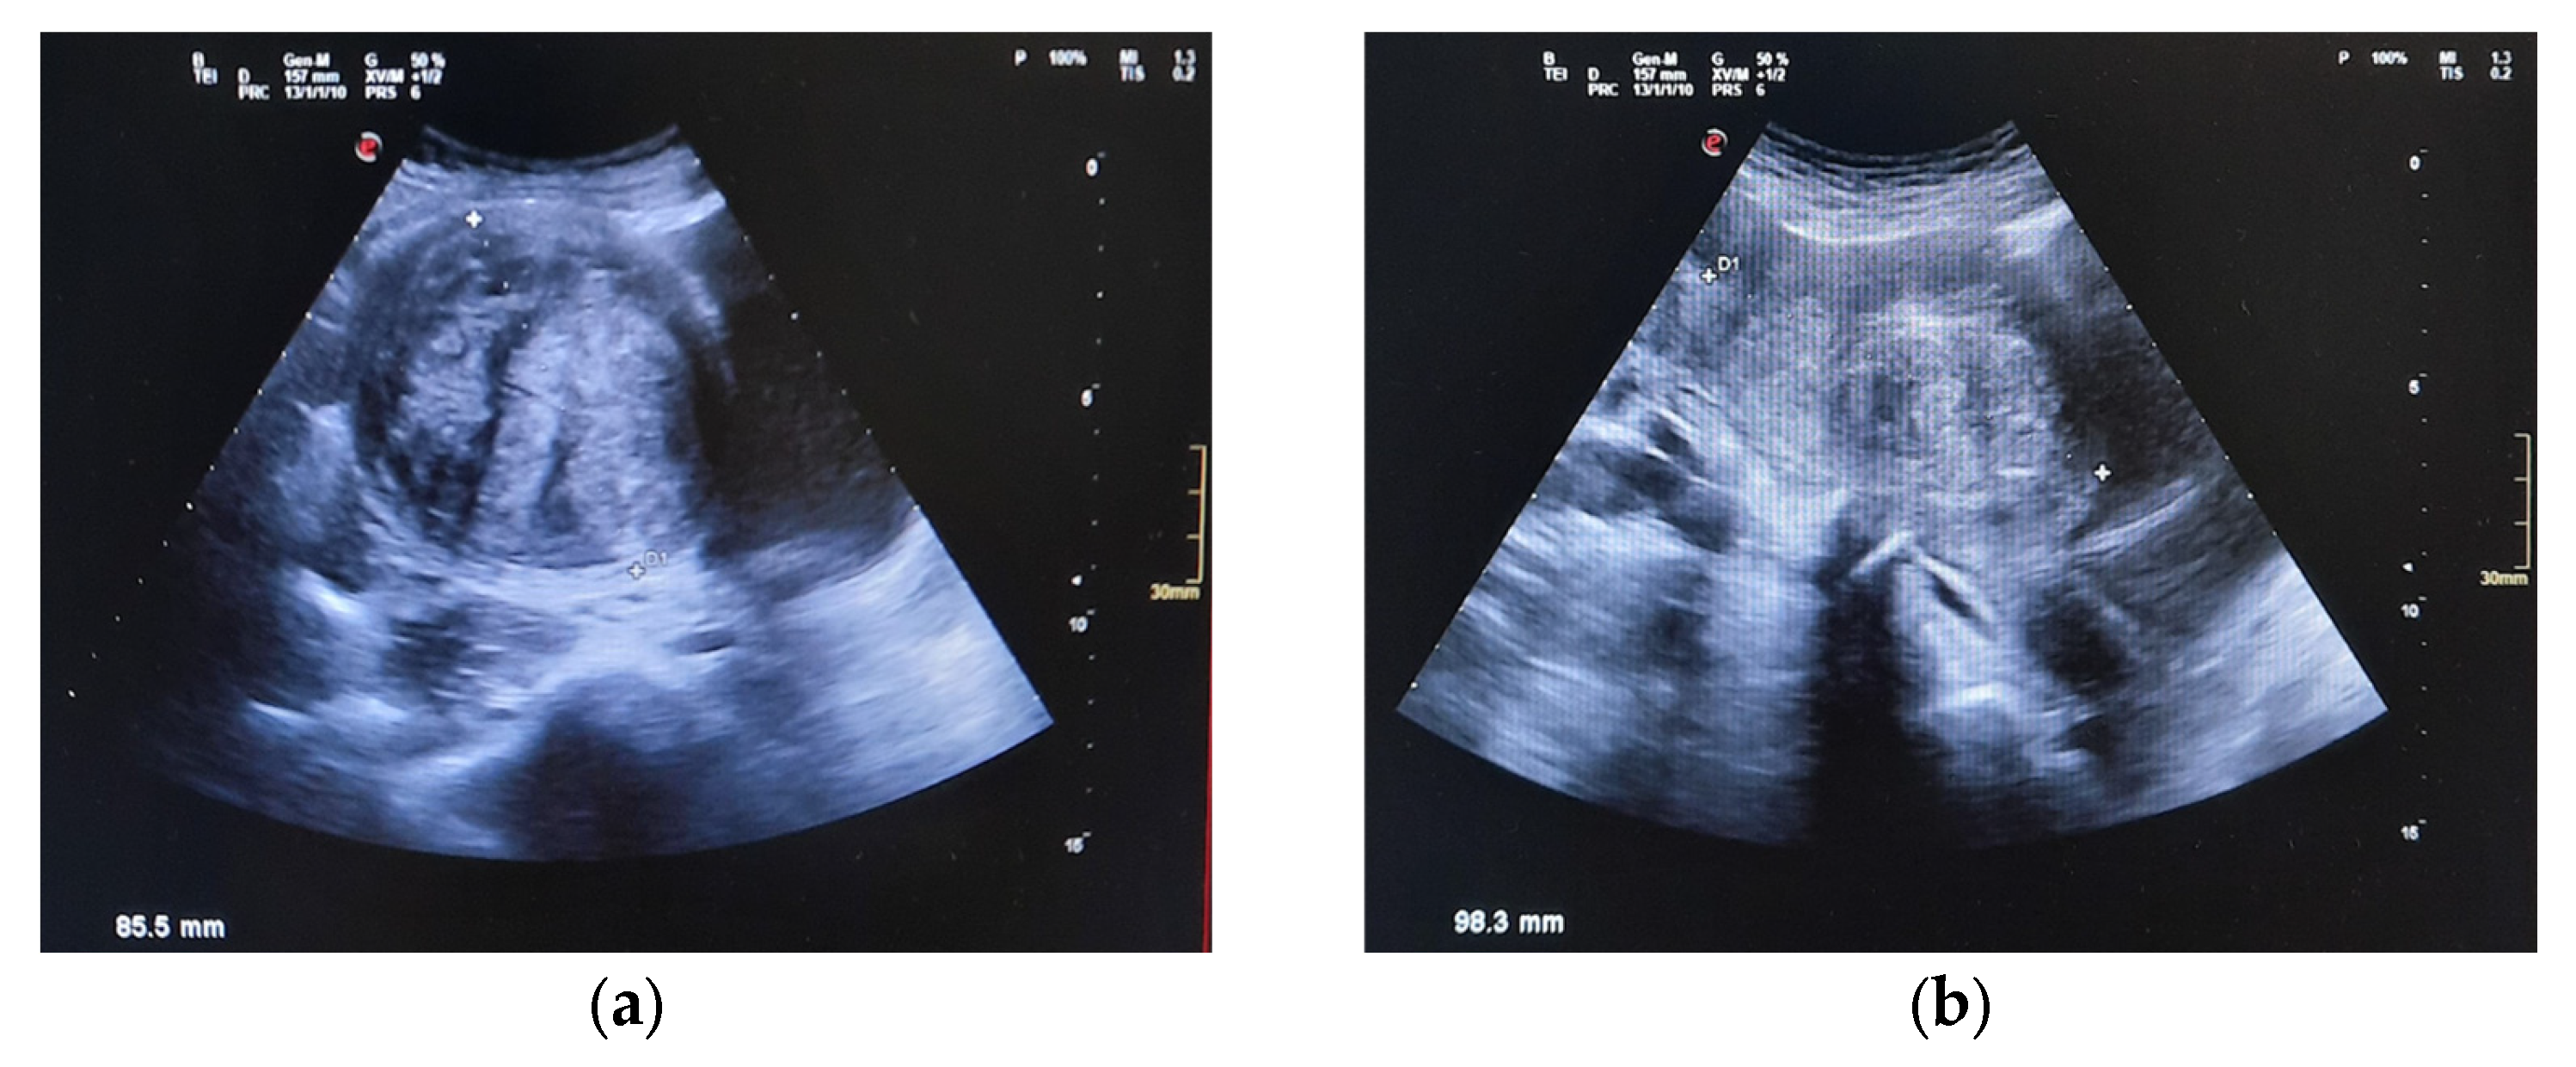

| 27 December 2024 | Abdominal US reveals 9 cm pelvic mass suggestive of fibroids; urgent gynecologic evaluation recommended. |

| ~July 2025 | Postoperative follow-up at 40 days: symptoms resolved; normal ultrasound; no pelvic pain or urinary issues. |